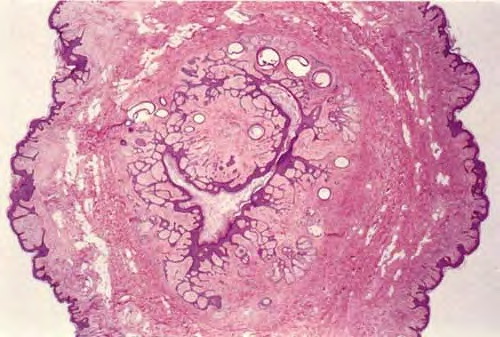

Trichofoliculoma =ورم جريبي شعري